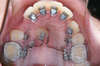

L'appareillage